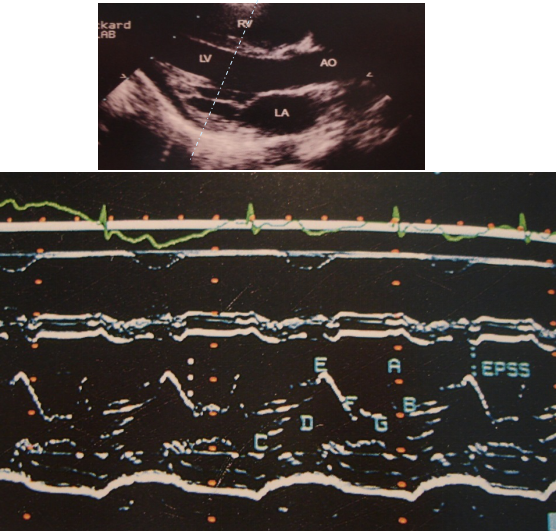

M型超声心动图

二维超声心动图

胸骨旁长轴切面 四腔心切面